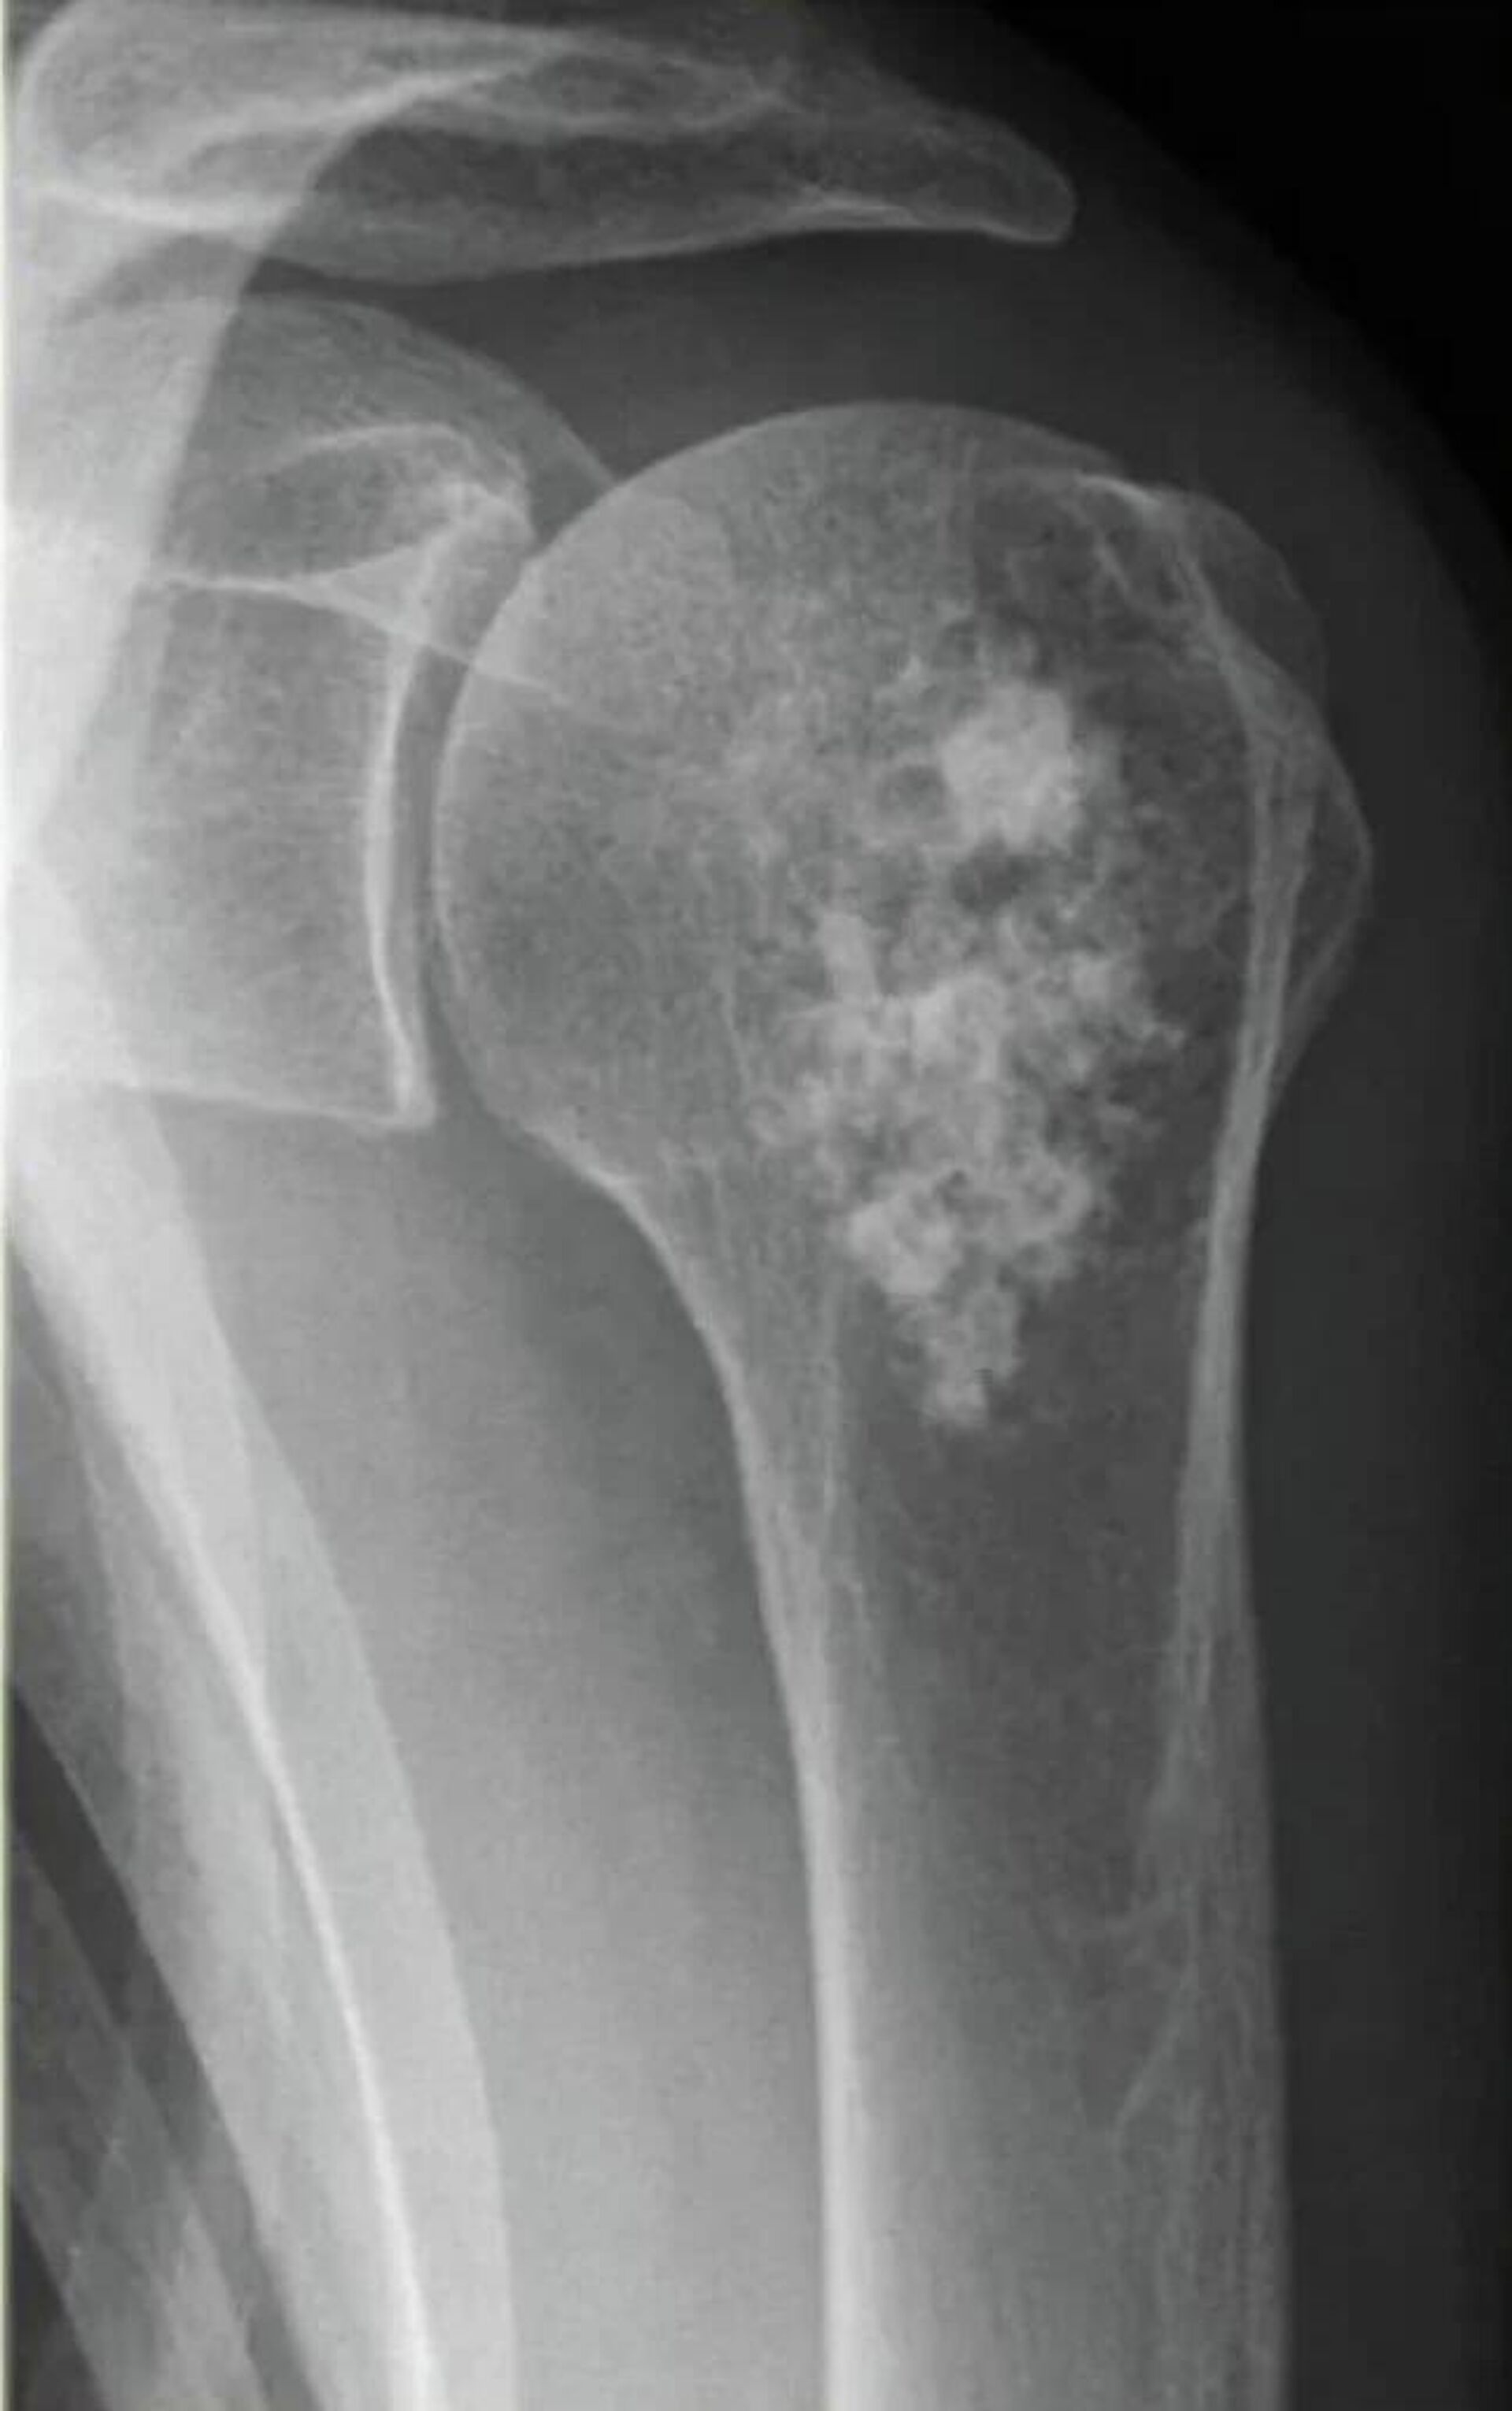

Препарат планируется использовать для лечения определенных видов онкологических заболеваний, преимущественно при метастазах в костях. И как рассказали в госкорпорации, "Ракурс" обладает двойным действием.

Во-первых, он уничтожает метастазы в костях, давая возможность человеку с диагнозом "рак предстательной железы" продлить жизнь на фоне заболевания, селективно накапливается в костях, включая костные метастазы. Результатом такого лечения становится высоколокализованный противоопухолевый эффект.

Во-вторых, радий-223 воздействует на болевой синдром и дает возможность отказаться от применения обезболивающей лекарственной терапии, что значительно повышает качество жизни пациента.